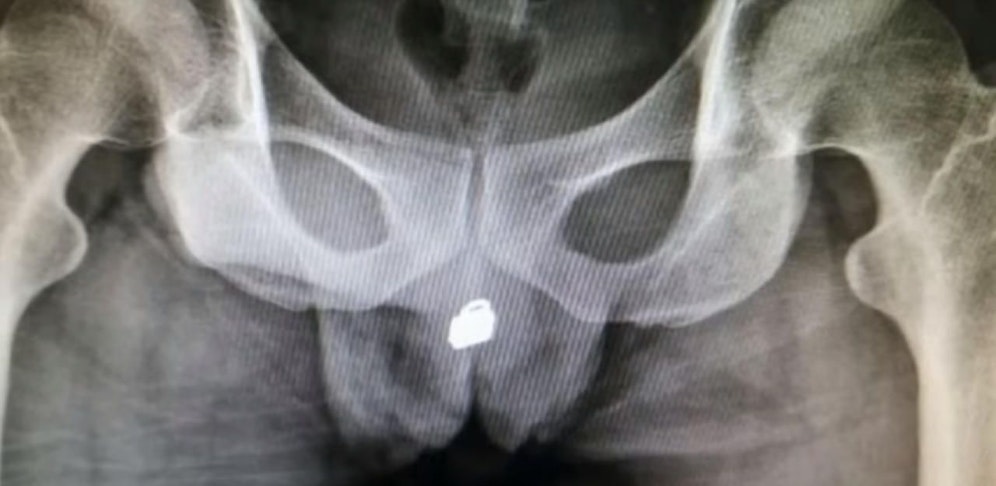

Die Ärzte des Spitals im chinesischen Fuzhou staunten nicht schlecht, als sie die Röntgenbilder des 31-Jährigen zu Gesicht bekamen. Der Mann hatte sich laut "The Sun"-Berichten im Rahmen eines Sexspielchens ein Vorhängeschloss in seine Harnröhre eingeführt.

Kurze Zeit später klagte er über enorme Schmerzen im Unterleib und begab sich selbst in ein Krankenhaus.

Der Mann musste operiert werden, glücklicherweise konnte das "Liebesschloss" schnell entfernt werden. Ob der 31-Jährige vom riskanten Liebesspiel bleibende Schäden davontragen wird, können die Ärzte Medienberichten zufolge noch nicht abschätzen.